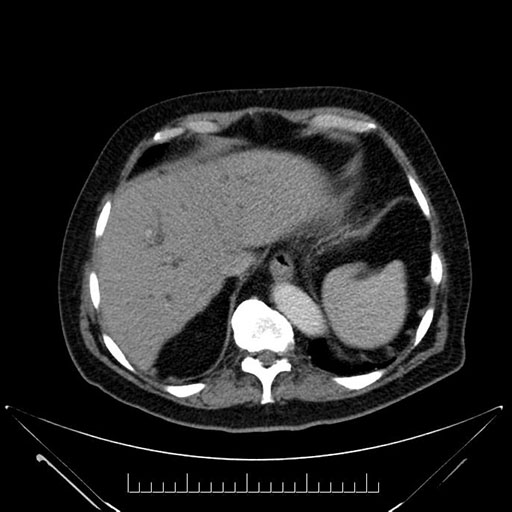

Whipple (pancreaticoduodenectomy) [case 7]

Axial - stented